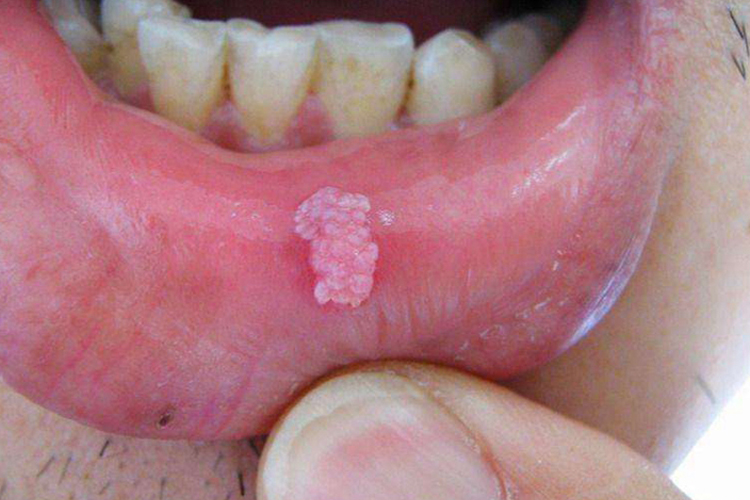

唇部有菜花状皮损可表现为嘴唇上有淡粉色、红色等大小不一的异常增生物。

尖锐湿疣:皮损初起为单个或多个散在的淡红色小丘疹,后逐渐增多、增大,并互相聚集但不融合,除呈现菜花状外,还可为乳头状、鸡冠状、蕈样状等多种不同形态。

唇癌:唇癌患者早期会出现疱疹状、结痂的肿块,随后可出现火山口状溃疡或菜花状的肿块,表面可为红色。以后肿瘤会向周围皮肤及黏膜扩散,同时向深部肌组织浸润。